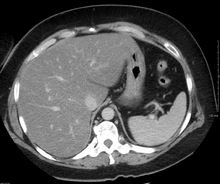

Imaging studies are often obtained during the evaluation process. Ultrasonography reveals a "bright" liver with increased echogenicity. Medical imaging can aid in diagnosis of fatty liver; fatty livers have lower density than spleens on computed tomography (CT), and fat appears bright in T1-weighted magnetic resonance images (MRIs). No medical imagery, however, is able to distinguish simple steatosis from advanced NASH. Histological diagnosis by liver biopsy is sought when assessment of severity is indicated.